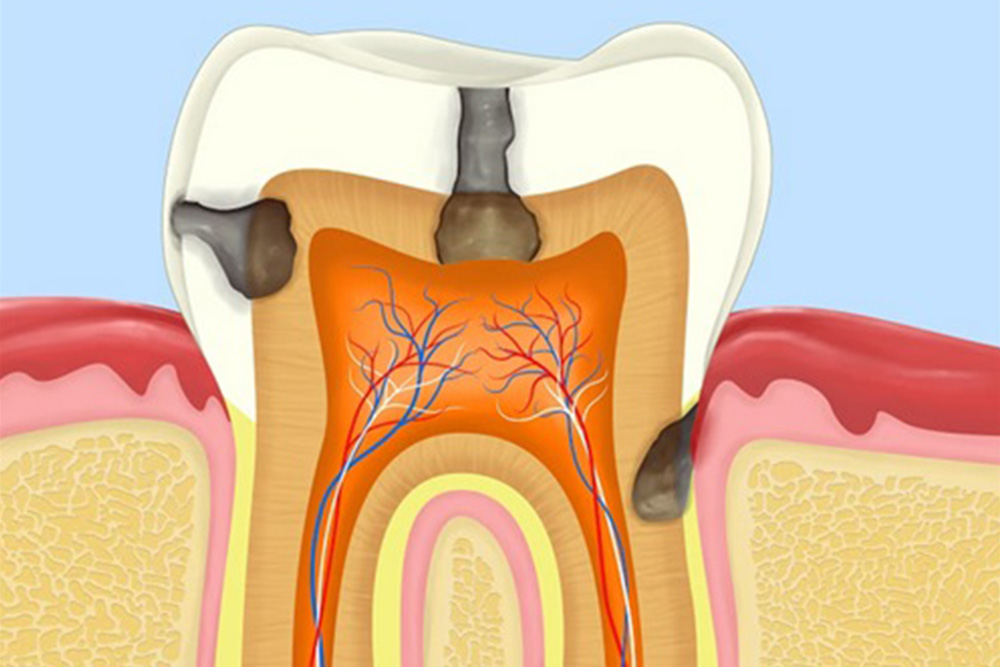

虫歯・歯周病になっている

親知らずはお口の一番奥に生えるため、ケアがしづらく、虫歯や歯周病リスクが高くなります。治療を行なっても、ケアがきちんとできなければ、何度も治療を繰り返すだけでなく、周囲の歯も虫歯や歯周病になりやすくなります。そのため、親知らずが虫歯や歯周病なっている場合には、抜歯をおすすめいたします。